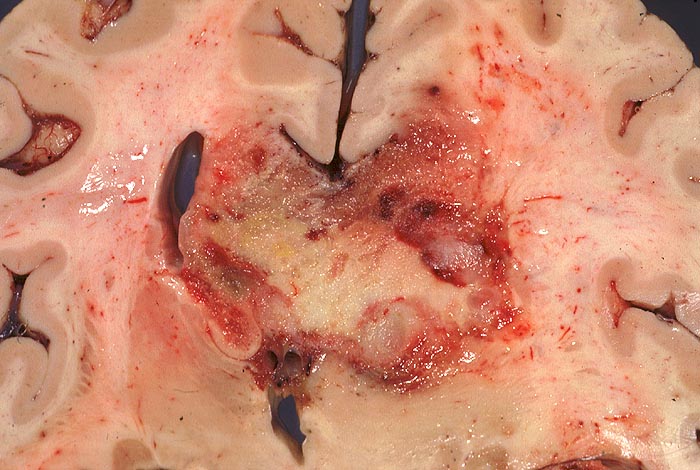

Morphologie:

Die Schnittfläche ist auffallend bunt. Dies ist bedingt durch ein Nebeneinander von graurotem vitalem Tumorgewebe, gelben Nekrosen, roten Einblutungen und gelegentlich grünlichen Gallertzysten.

Makroskopie